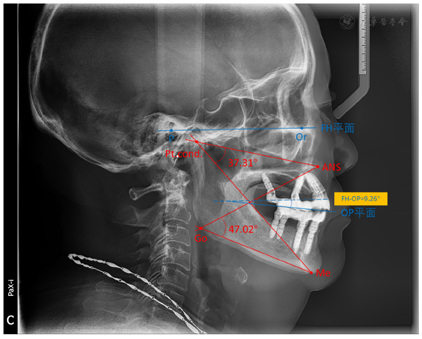

,患者咬合关系稳定,行使功能良好。此外,Orthlieb等[16]通过对505名正常成年人进行X线头影测量分析后发现,ANS-Go-Me角可以用来衡量咬合垂直距离。研究发现,垂直距离的上角(VDO sup,从髁点到ANS和颏点连线的交角)的均值为40±3.88°,垂直距离的下角(VDO inf,从下颌角点到ANS和颏下点连线的交角)的均值为48.5±5.21°。拍摄侧位片(图22),头影测量得出患者VDO sup为37.31°,VDO inf为47.02°,均在上述均值范围内,可认为患者垂直距离恢复良好。此外,

平面斜度过大易导致下颌后旋、后牙段磨损,理想的FH-OP角度为10°左右[17],本病例FH-OP角度为9.26°,可认为患者

平面角度正常。